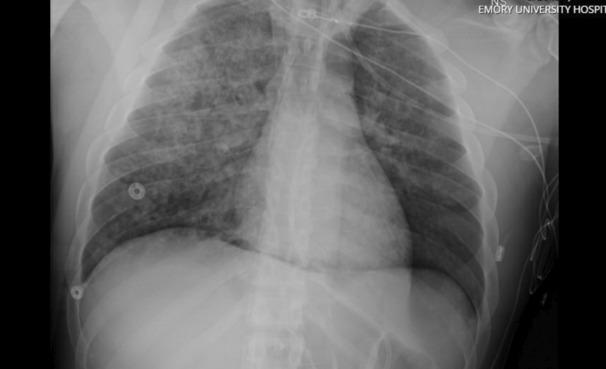

Negative pressure pulmonary edema (NPPE) may result in respiratory failure refractory to conventional management strategies. Venovenous extracorporeal membrane oxygenation (VV ECMO) can serve as a rescue therapy in cases of severe respiratory failure. Rapid initiation of VV ECMO can decrease morbidity and mortality while facilitating early liberation from mechanical ventilation and promoting early rehabilitation. We describe the successful utilization of VV ECMO as rescue therapy for severe NPPE-induced hypoxic respiratory failure and peri-arrest state in the postanesthesia care unit (PACU) in a patient with postextubation airway obstruction after undergoing patellar tendon repair.

负压性肺水肿(NPPE)可能导致对传统治疗策略无效的呼吸衰竭。静脉-静脉体外膜肺氧合(VV ECMO)可作为严重呼吸衰竭病例的一种挽救治疗方法。快速启动VV ECMO可降低发病率和死亡率,同时有助于早期脱离机械通气并促进早期康复。我们描述了在一名接受髌腱修复术后拔管后气道梗阻的患者中,成功将VV ECMO用作麻醉后护理单元(PACU)中严重NPPE引起的低氧性呼吸衰竭和濒死状态的挽救治疗方法。